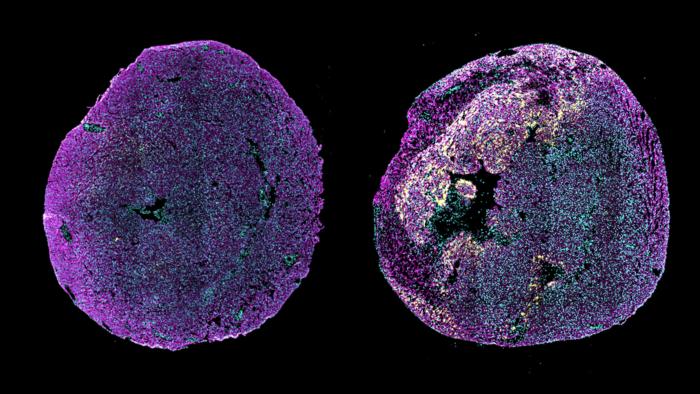

Источник: Cheng Lab/Columbia University. Иммунофлуоресцентное изображение поперечных срезов сердца здоровой новорожденной мыши (слева) и новорожденной мыши, у которой инфаркт миокарда был вызван в первый день после рождения; анализ проведен через три дня после повреждения (справа). Желтый сигнал показывает высокий уровень экспрессии pro-ANP в пограничной зоне поврежденного миокарда. Pro-ANP — это белок, уровень которого повышается в ответ на повреждение и который способствует восстановлению сердца у новорожденных мышей. Кардиомиоциты показаны пурпурным цветом (α-актинин), а клеточные ядра — голубым.